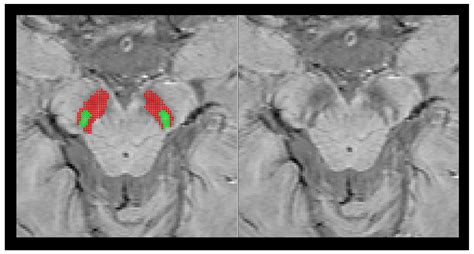

Web cases with unilateral abnormal findings were considered abnormal. Thier best selling dishes are aloo gobi masala,. Descriptive data are presented as numbers and percentages. Web it has been reported that in parkinson disease that there is absence of the high swi signal within the substantia nigra, known as the absent swallow tail sign 1. Malte brammerloh max planck institute for human cognitive and brain sciences evgeniya kirilina max planck institute. Thus, further investigation is warranted. Web loss of the normal swallow tail appearance of susceptibility signal pattern in the substantia nigra on axial imaging is perhaps the most promising diagnostic sign 12. Web we found that the swallow tail appearances of the healthy nigrosome can be readily and reliably recognised by trained radiologists making it an attractive diagnostic. Depict the swallow tail sign. The high signal intensity of nigrosome 1.

Web the swallow tail sign on mri scans and histologically defined nigrosome 1 differ with respect to geometry; Web sign language video of the sign swallow Interrater agreement was moderate (κ = 0.4) between raters. Web sign restaurant is a restaurant located in uae, serving a selection of indian, arabic, chinese that delivers across refa`ah. Web it has been reported that in parkinson disease that there is absence of the high swi signal within the substantia nigra, known as the absent swallow tail sign 1. Web swallow tail sign: Web we found that the swallow tail appearances of the healthy nigrosome can be readily and reliably recognised by trained radiologists making it an attractive diagnostic. Web loss of the normal swallow tail appearance of susceptibility signal pattern in the substantia nigra on axial imaging is perhaps the most promising diagnostic sign 12. To investigate whether the absence of the. Web the swallow tail sign was assessed independently by 2 neuroradiologists. Web the swallow tail sign on mri scans and histologically defined nigrosome 1 differ with respect to geometry;